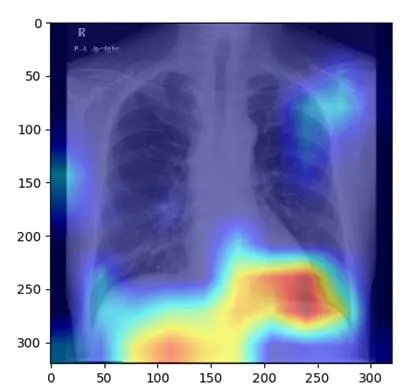

Bundling of RACOON and SPP2177 revolutionizes AI-supported radiology

The Germany-wide RACOON network and the Priority Programme SPP2177 are joining forces to accelerate and refine the evaluation of radiological image data by artificial intelligence (AI). The aim is to decisively improve diagnostics and therapy through novel,...